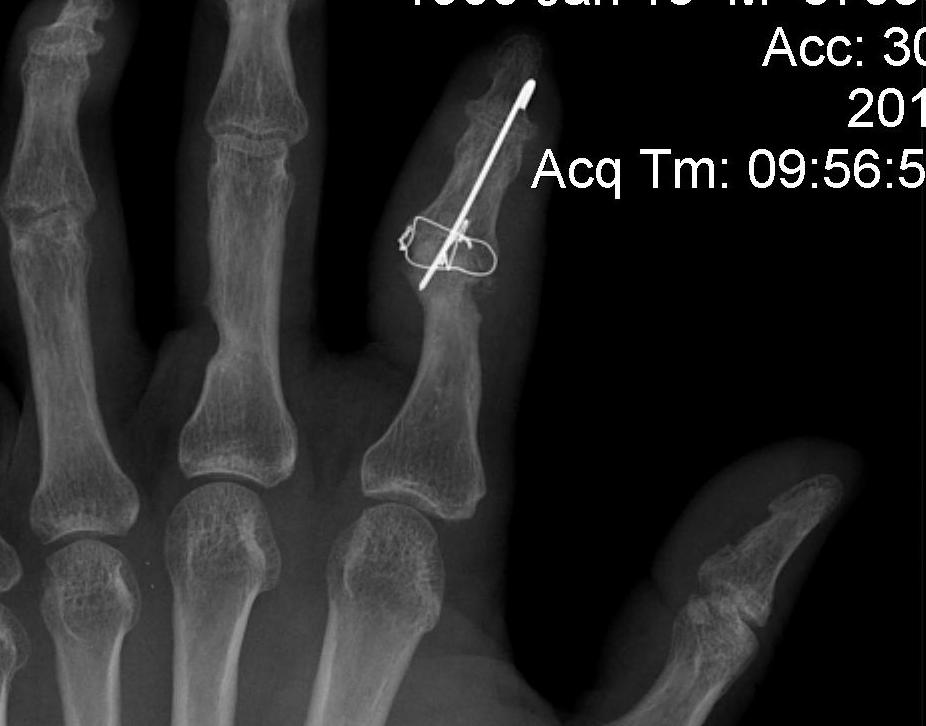

A. Headless compression screw

B. K wire and TBW

B. Crossed K wires

C. Longitudinal K wire and TBW figure 8